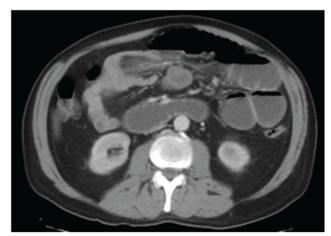

En la tomografía computada (TC) de abdomen y pelvis con contraste intravenoso se observan: asas yeyunales distendidas, con niveles hidroaéreos en su interior. Transición asa chata- asa distendida a nivel de epigastrio. Sin neumatosis parietal, ni neumoperitoneo. Se identifican dos engrosamientos nodulares peritoneales de 25 mm x 38 mm y 30 mm x 40 mm en epigastrio. Escasa cantidad de líquido libre interasas y en FSD. (Fig.1)

Fig 1 TC de abdomen y pelvis que evidencia intususcepción de intestino delgado.